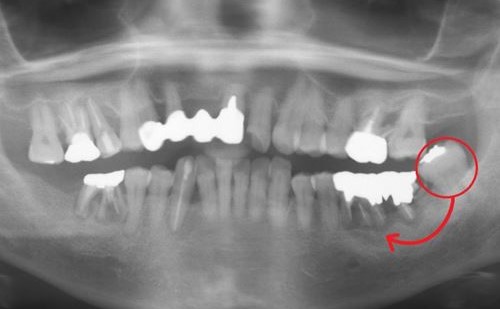

術前X線画像(パノラマ)

術前X線画像:症例2-2

術前X線画像